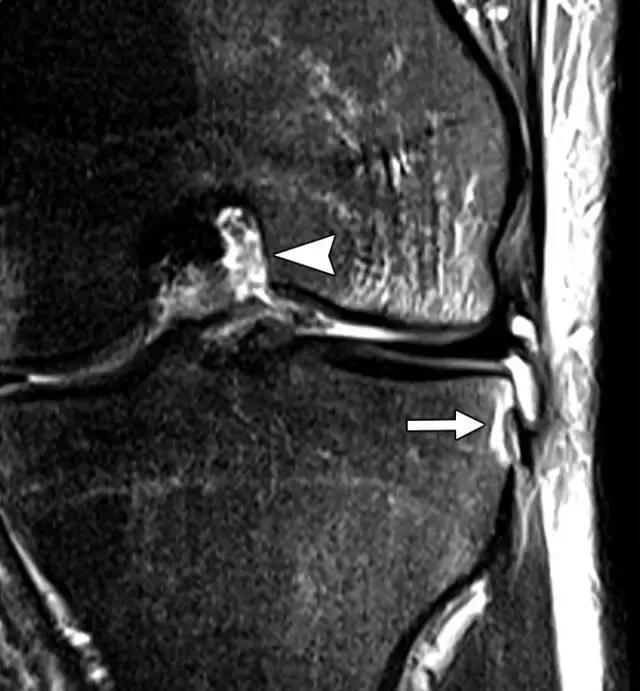

在放射照片上,Segond骨折显示为邻近近侧外侧胫骨平台的小骨片,并且在膝关节的前后放射照片上能很好的显示(图5A)。在MR图像上,由于相邻软组织中突出的异常信号强度,小的撕裂片段可能不像放射照片那样显着(图5B),但膝关节内更重要的损伤可以更好地显示。在75-100%的Segond骨折患者中发现ACL的撕裂,66-75%的病例中同时存在半月板损伤。

图5A -30岁的Segond骨折患者。A,膝关节前后位X线照片显示沿胫骨外侧平台的薄线状骨折片段(箭头)。

图5B骨折挫伤存在于股骨外侧髁上,前交叉韧带可以看到较低低信号,表明撕裂(箭头)。